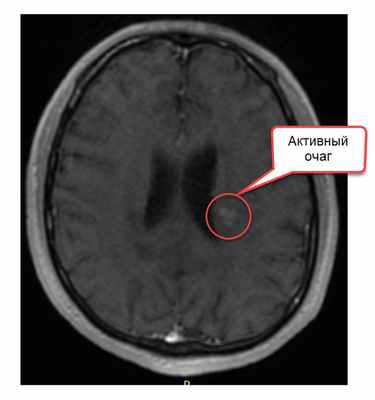

Наконец необходимо уточнить, что такое контрастное вещество. Это раствор, содержащий атомы гадолиния – металла, обладающего определенными магнитными свойствами. При его введении внутривенно, атомы металла проникают по кровяному руслу в сосуды головного мозга. Если очаг демиелинизации только появился, если в нем происходит воспаление, то мелкие сосуды, находящиеся в очаги проницаемы – у них не функционирует гематоэнцефалический барьер. И тогда в этот очаг начинают проникать атомы гадолиния, а в другие (старые) очаги не проникают, так как в сосудах старых очагов гематоэнцефалический барьер уже восстановился. На Т1-изображении зоны, где скапливаются атомы гадолиния, приобретают белый цвет, тогда мы говорим, что на изображении есть активные очаги.

- очаг на Т2-изображении, накапливающий контраст на Т1-изображении

- выявление при одном исследовании очагов накапливающих и не накапливающих контраст